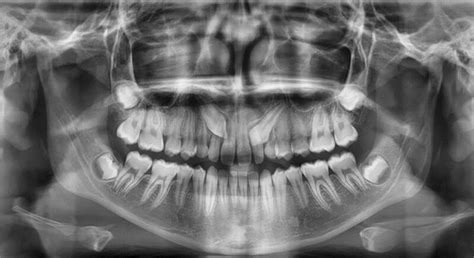

El primer paso es el estudio en profundidad del caso. Para ello, se solicitan radiografías, como las panorámicas o tomografía computerizada (TAC); herramientas esenciales para evaluar la posición y la trayectoria de erupción de los caninos incluidos.

Como mencionamos antes, algunos pacientes que presentan dientes impactados no presentan ningún tipo de dolor u otros malestares, aunque se ven a simple vista, especialmente cuando ocurre en los dientes caninos. El profesional puede examinar la zona y con ayuda de muestras radiográficas determinar el procedimiento a seguir.

Después de las muelas del juicio, los caninos superiores son los dientes más afectados en cuanto a su impactación. Los caninos incluidos son relativamente frecuentes: son dientes que, por diversas causas, no erupcionan correctamente en boca y se quedan «dentro del hueso».